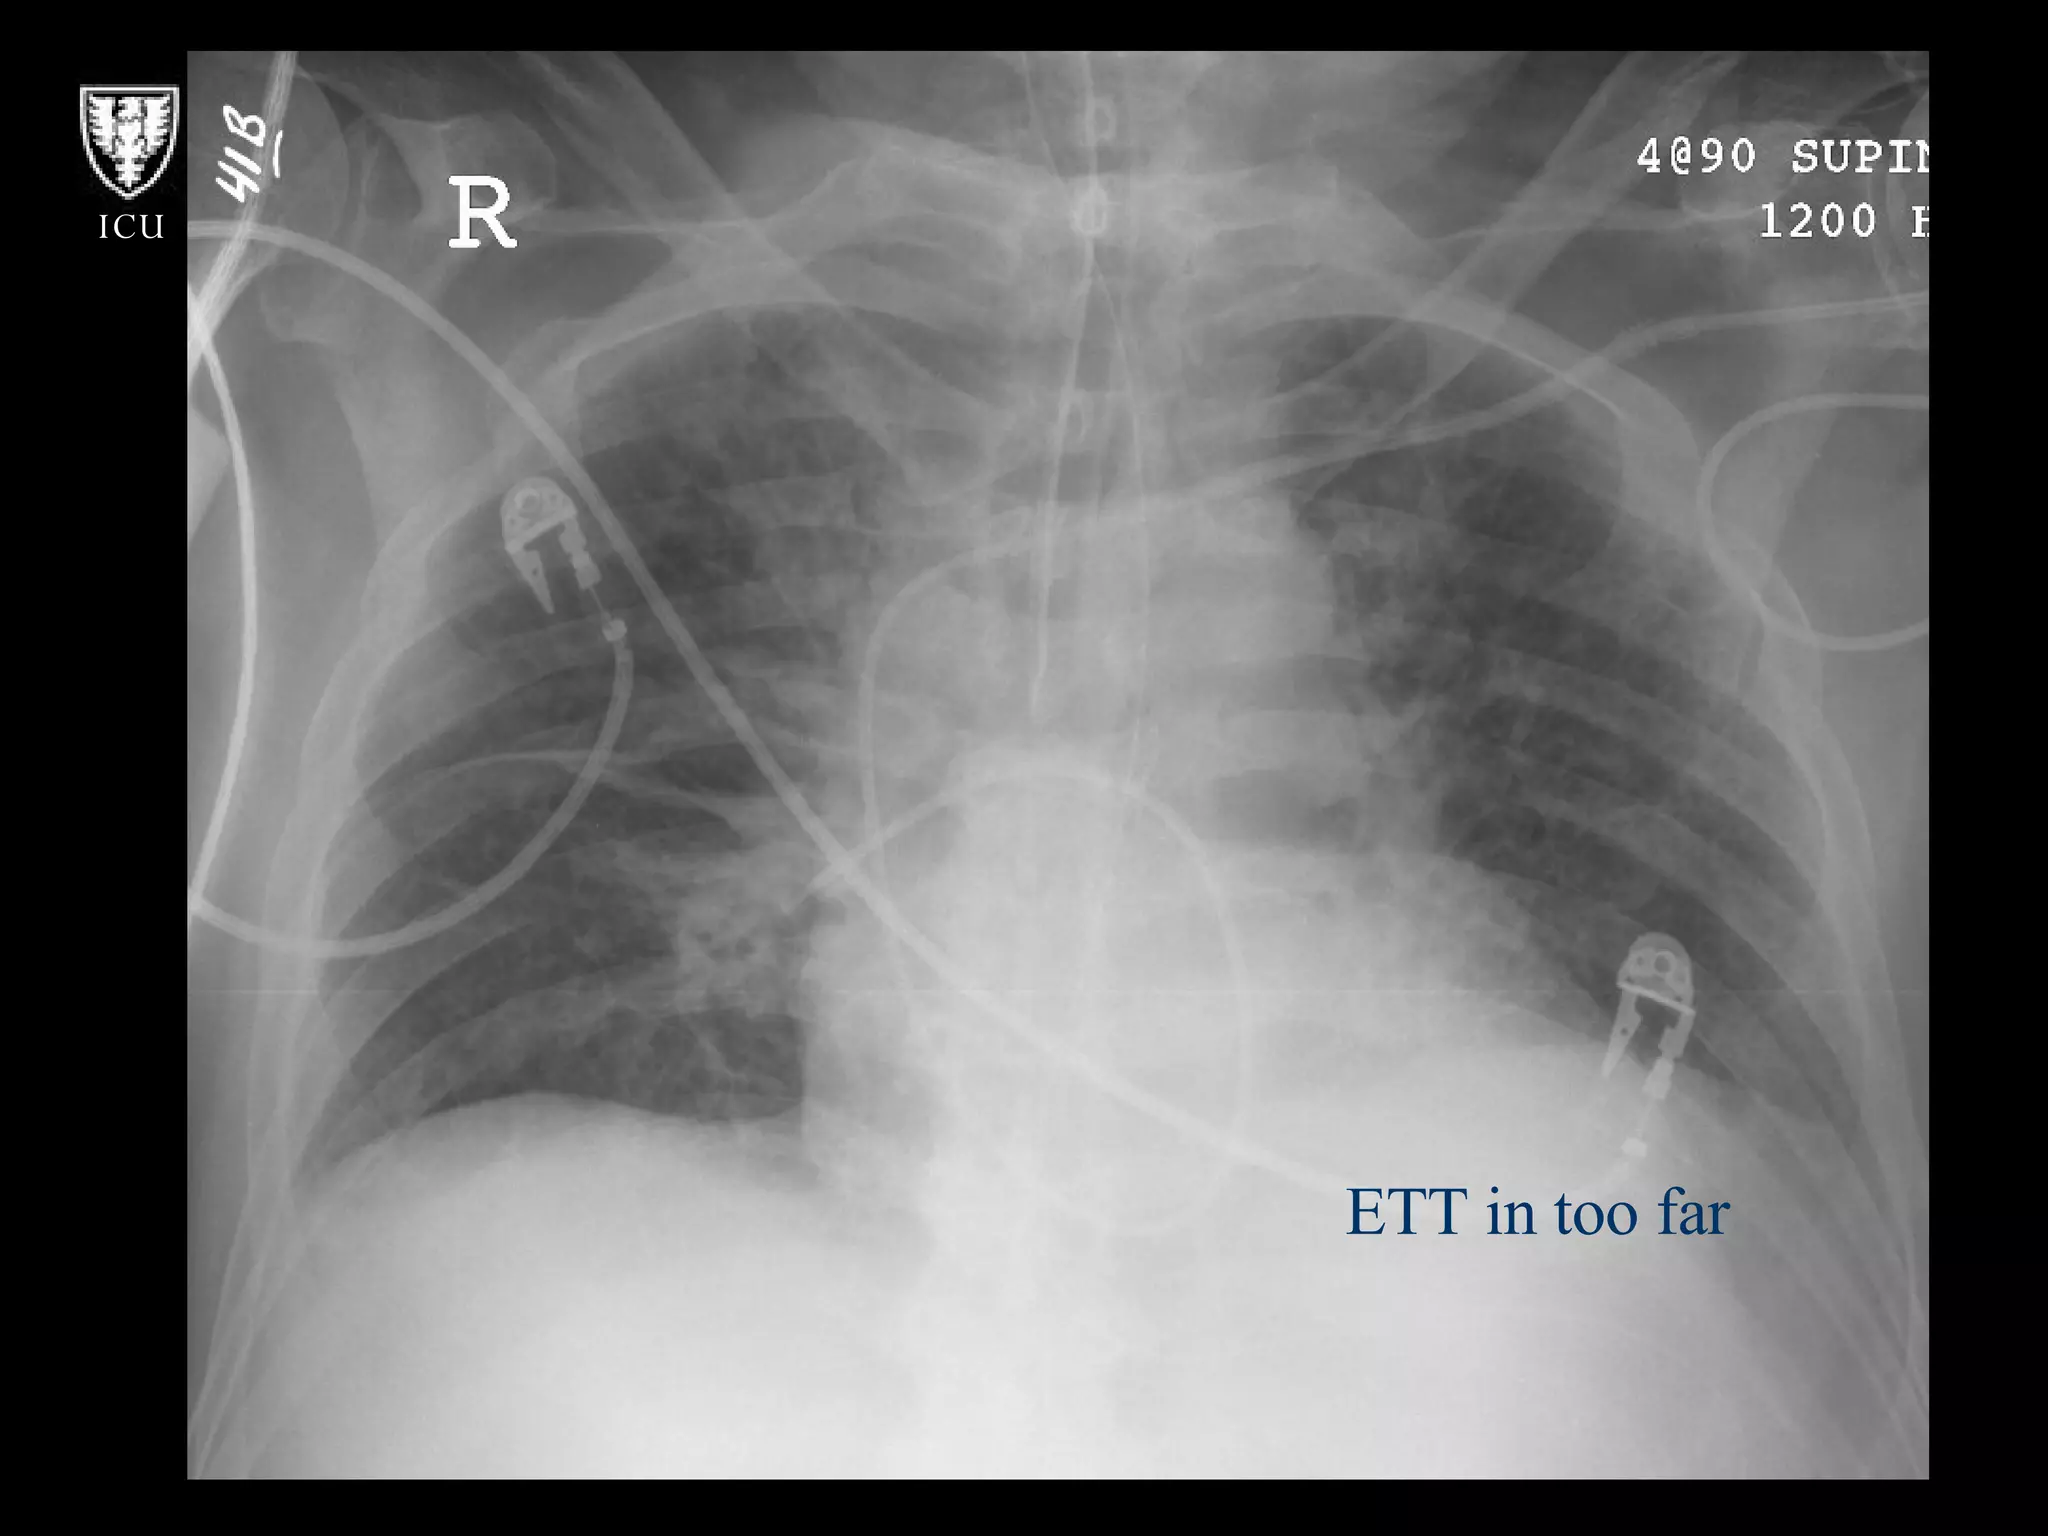

What’s Wrong With These Pictures?

ETT in too far

What’s Wrong WithThese Pictures?